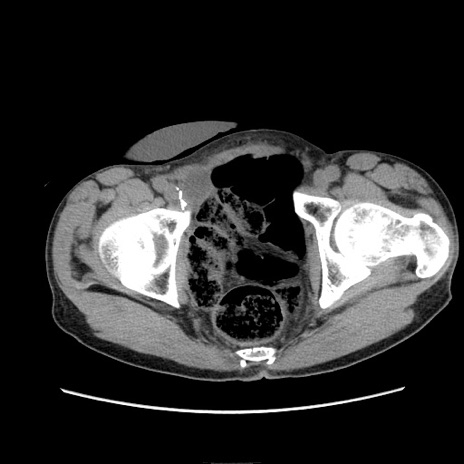

冠状断像

【症例】 60歳代男性

【主訴】 下腹部痛

【現病歴】 本日夜中より下腹部痛の症状認め、受診。

【既往歴】 膀胱癌(膀胱全摘+尿管皮膚瘻術) 、胃癌術後

【身体所見】 BT 35.3℃、PR 58/min、BP 136/98mHg、腹部平坦、軟、腸蠕動音±、ストマ留置あり、左上腹部~正中部に圧痛あり、反跳痛なし。

【データ】WBC 5100、CRP0.01